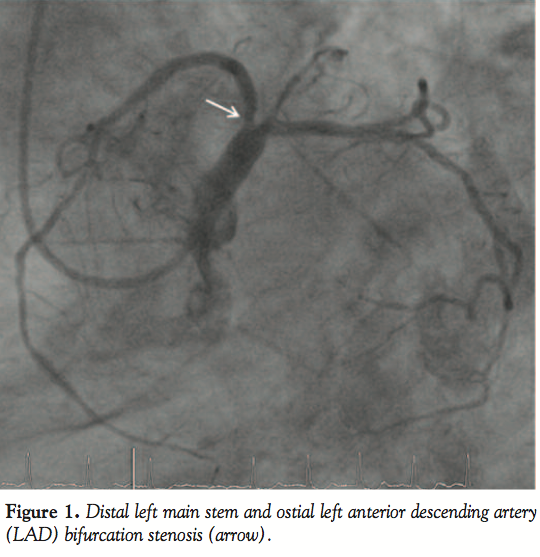

The current coronary angiogram revealed again a significant in-stent restenosis at this site as well as a significant de novo ostial LAD stenosis involving part of the distal LM stem (Figure 1). The left circumflex (LCX) coronary artery, including the ostial segment, was free of significant disease. The mid and distal LAD stents were widely patent and the left ventricular systolic function was normal.

The ostium of the LM stem was engaged using the same 5 Fr guiding catheter and guidewire. The tip of the wire was positioned into a septal branch of the LAD. The distal LM and ostial LAD were predilated using the same balloon at 24 bar. An Orsiro 3.0 x 9 mm stent (Biotronik AG) was placed in the lesion. The external end of the Magnum guidewire was connected to the cathode (negative pole) of a single-chamber Medtronic 5348 temporary pacemaker (Medtronic, Inc) with an alligator clamp, whereas the anode (positive pole) was connected to a large surface skin electrode at the left thigh of the patient. Pacing was instituted at 180 beats per minute, with output set at maximum (20 mA) and sensitivity turned off. The awake patient felt no discomfort. During rapid pacing, the stent was deployed using 14 bar for an inflation duration of 10 seconds (Figure 2). The mean arterial pressure was decreased to 40 mm Hg and the pulse wave to around 10 mm Hg (Figure 3). Rapid pacing was stopped with balloon

deflation. Angiography revealed a good result in the distal LM stem and ostial LAD, but the ostial LCX was now compromised owing to the carinal plaque shift (Figure 4). The Magnum guidewire was therefore repositioned across the ostial LCX into the first obtuse marginal branch of the LCX and the 3.0 x 9 mm stent balloon was used to fenestrate the side branch (ostial LCX) with 20 bars. Because the result was suboptimal, a second Orsiro 3.0 x 9 mm stent was positioned with its proximal portion located at the junction of the LM stem with the ostial LCX. The external portion of the Magnum guidewire was again connected to the temporary pacemaker and rapid pacing was instituted at 180 beats per minute to optimally position the stent at 14 bar (Figure 5). An excellent angiographic result was achieved in the LCX, but there was slight impingement of the ostial LAD (not shown). Therefore, the LAD was rewired and the ostial LAD was postdilated using the 3.0 x 9 mm stent balloon. An excellent angiographic result was achieved (Figure 6).